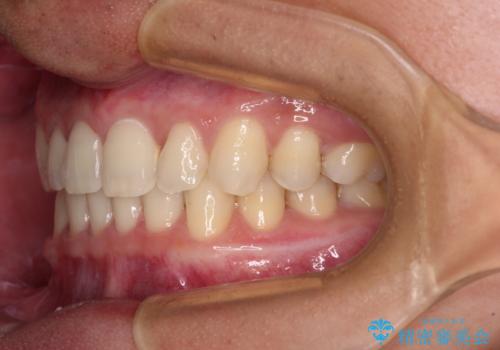

著しいディープバイトと隙間だらけの歯列

- 歯のデコボコと歯の隙間を気にして来院された患者様です。

隙間の原因は、埋伏や前後に重なってしまっている上顎小臼歯と、下の前歯が見えなくなるくらいのディープバイトで、それらを改善する必要がありました。

顕著なディープバイトのため、頻繁に装置が脱離することがあり、治療期間が想定よりも長くかかることがありますが、当初の予定期間で無事に治療を終えることができました。